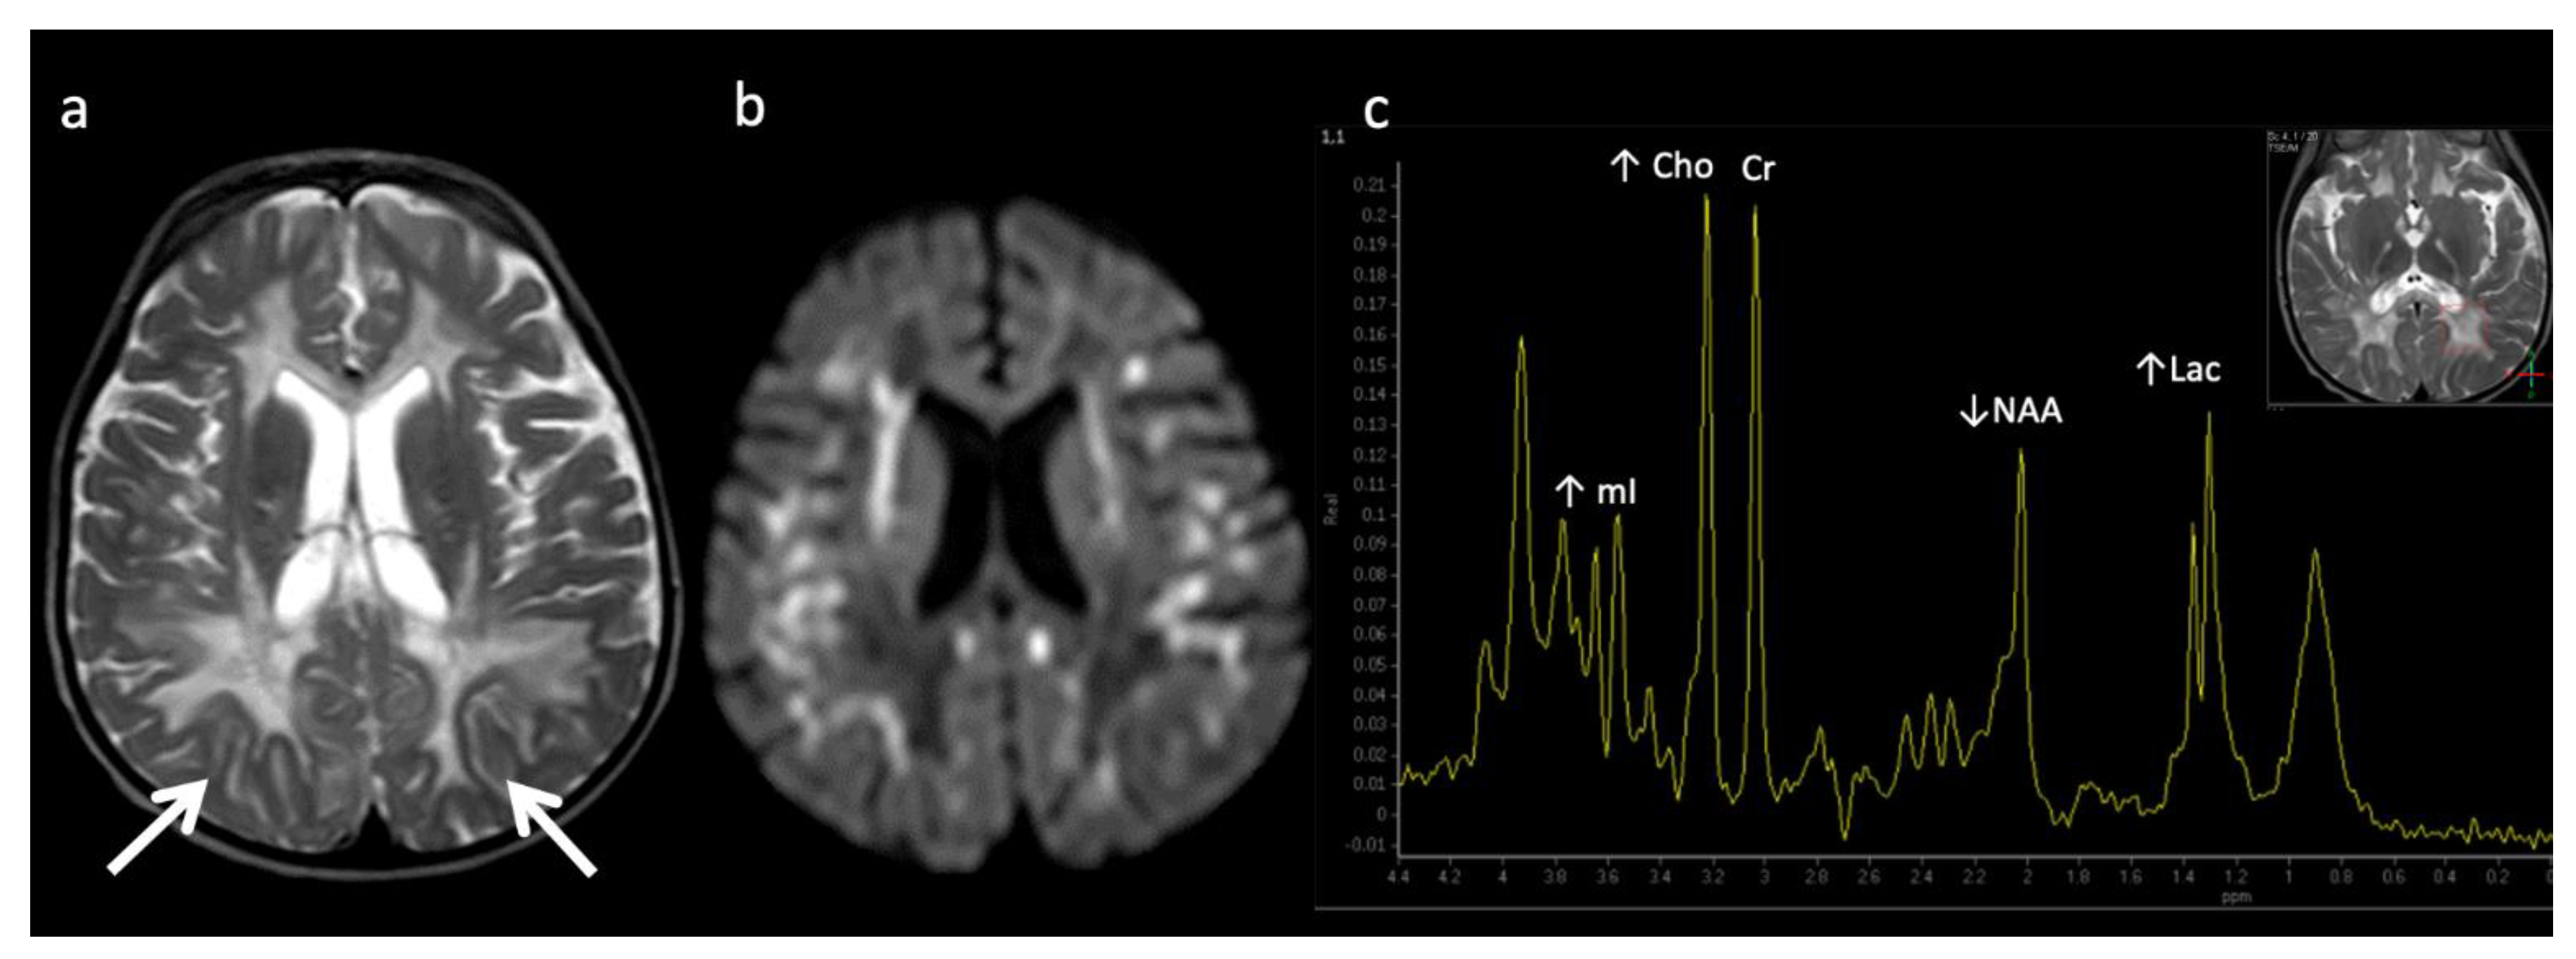

Figure 7.

Metachromatic leukodystrophy in a 16-month-old female who presented with loss of developmental milestones. (a) Axial T2WI and (b) axial DWI demonstrate cerebral volume loss with ex vacuo ventriculomegaly, a widespread leukodystrophy with increased white matter signal sparing the U-fibers (arrows) and involving corpus callosum, and reduced diffusion at leading-edges of active demyelination. (c) SV-MRS over the left periatrial white matter shows elevated Lac, severely depleted NAA, and slightly elevated Cho and mI. Findings are consistent with considerable axonal damage and loss of the white matter.